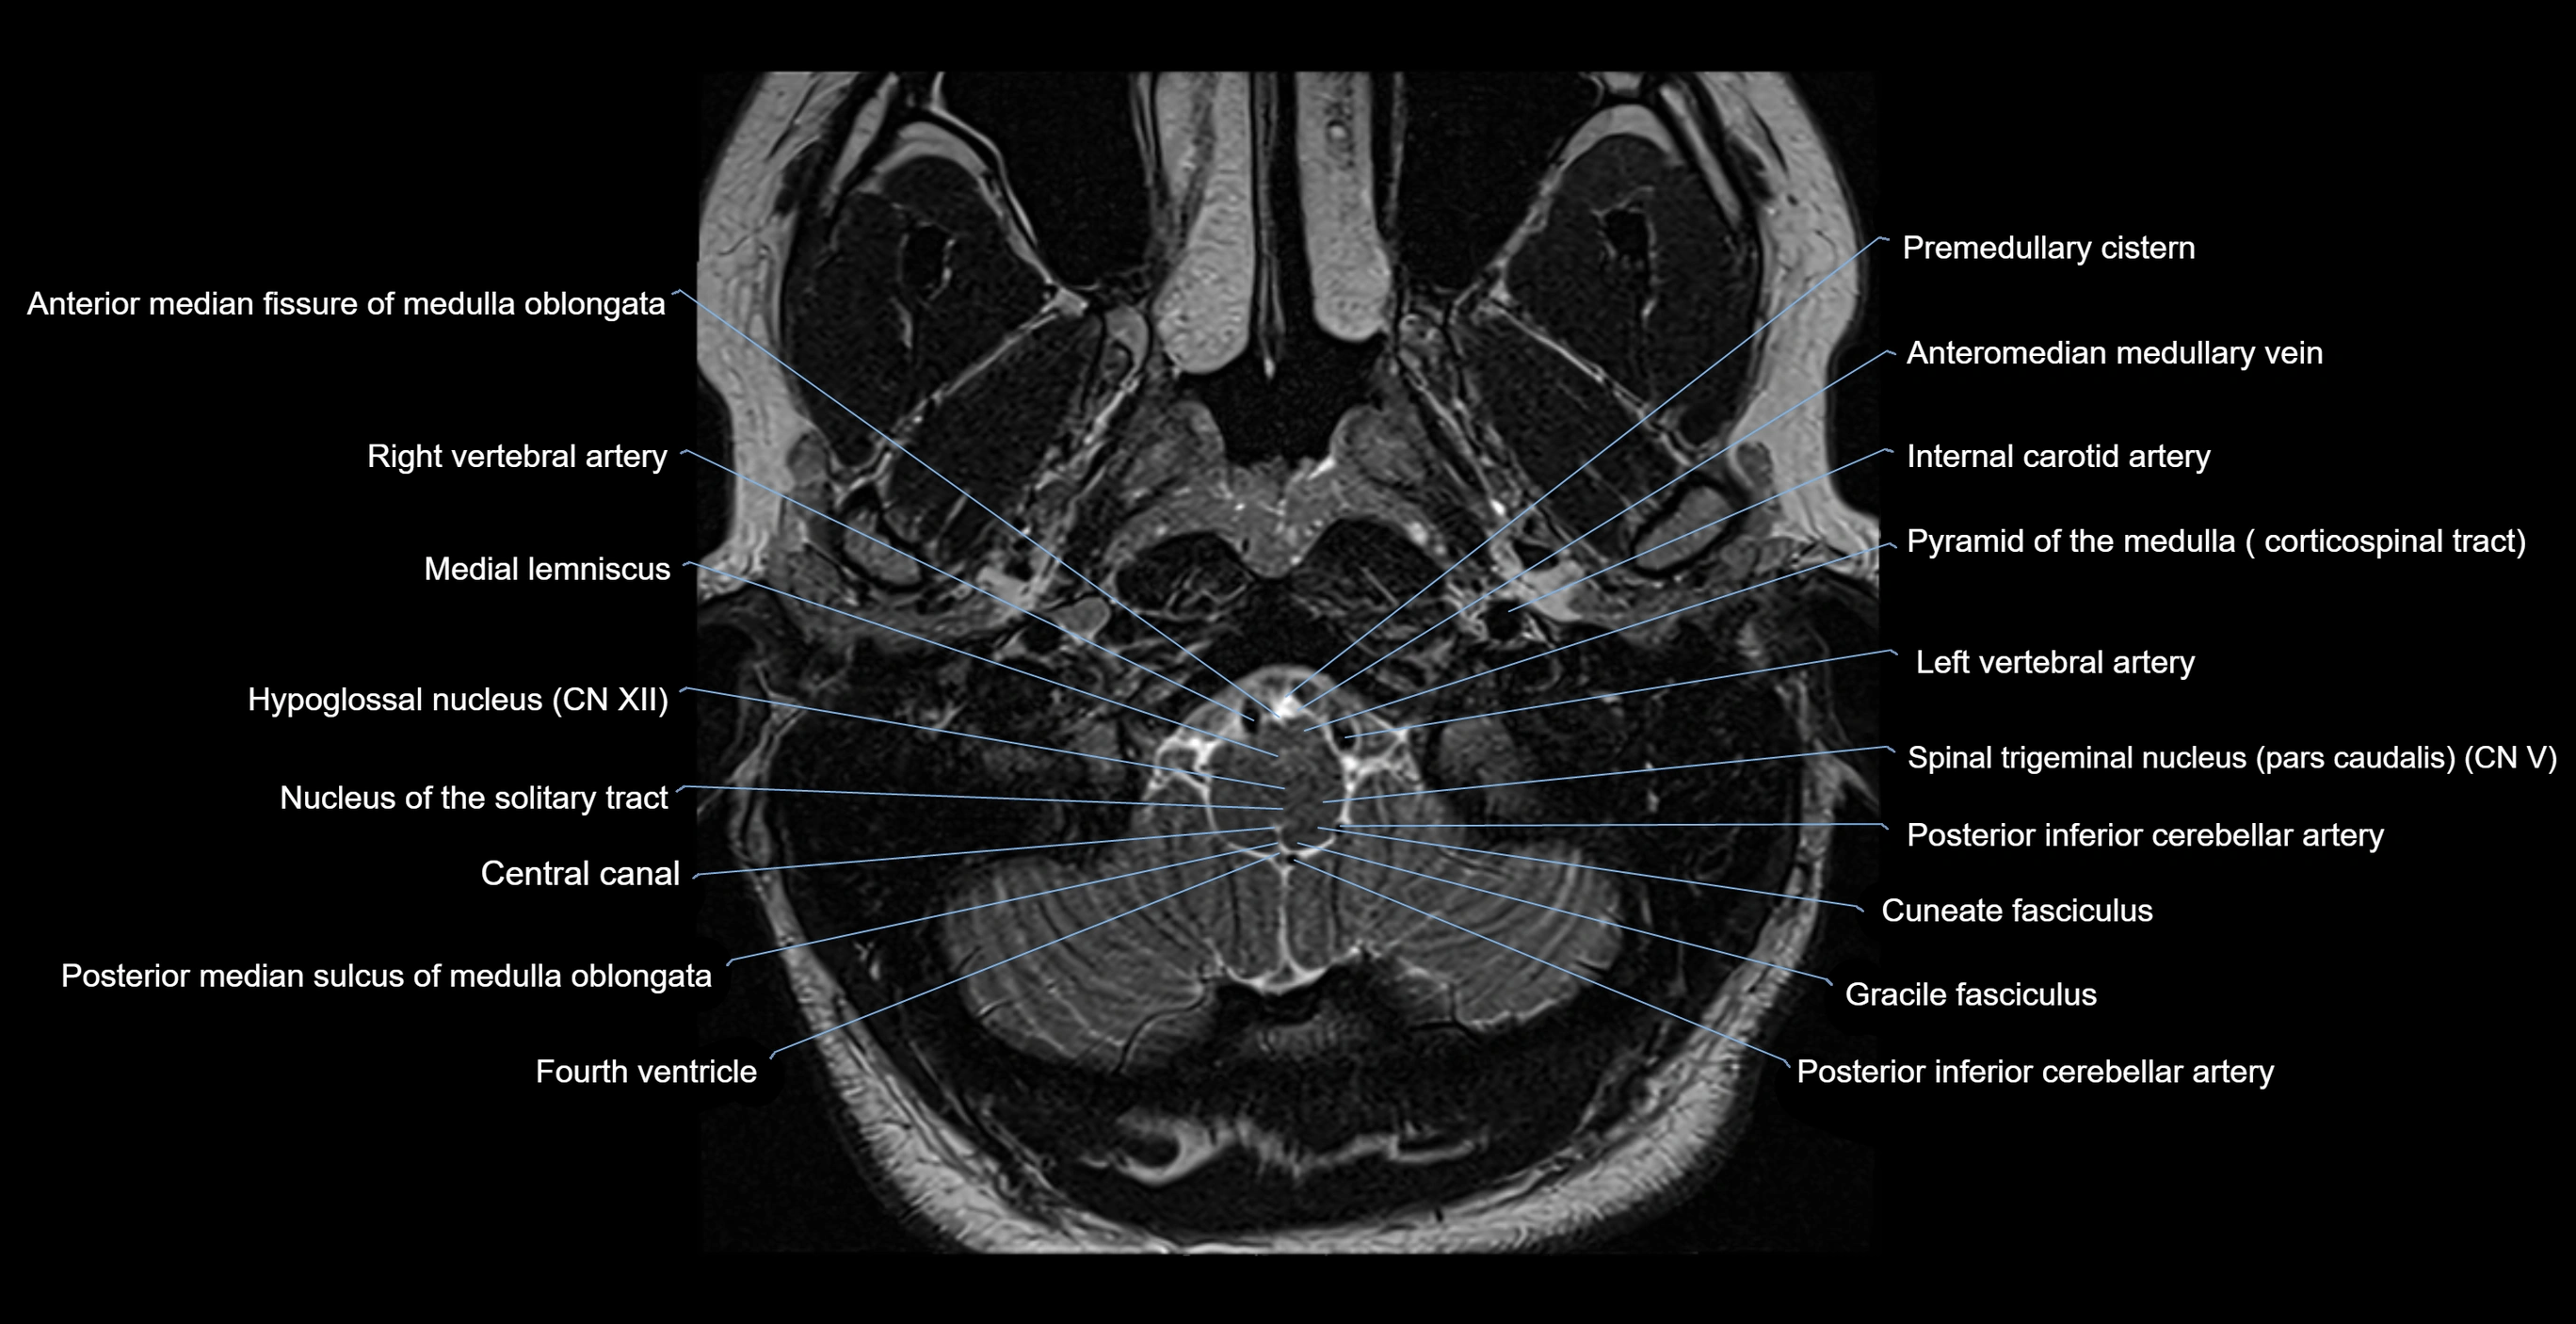

MRI images